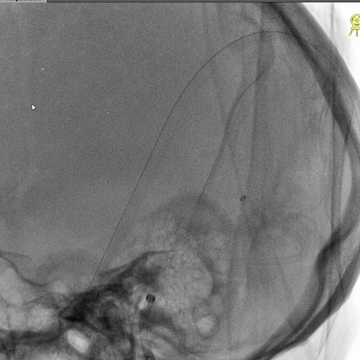

完成抽吸后,中间管和微导管直窦内造影均显示直窦管腔部分再通,恢复引流,但直窦近段存在狭窄。

经微导管送入并释放取栓支架(S AB 6*30mm),并在直窦取栓一次,取出少量碎小红色血栓。

微导管配合下,微导丝通过长段慢性血栓进入上矢状窦前部真腔,后交换出微导管。

3*30mm球囊扩张上矢状窦中前部管腔,辅以球囊滑动技术。

4*30mm球囊扩张上矢状窦中前部管腔,辅以球囊滑动技术。

5*30mm球囊扩张上矢状窦和右侧横窦-乙状窦,辅以球囊滑动技术。

中间管造影:上矢状窦中后部和右侧横窦-乙状窦血液引流可。

微导丝微导管再次超选直窦,造影示直窦近段狭窄。

3*30mm球囊再次扩张直窦近段,辅以球囊滑动技术。

球囊扩张直窦后造影:直窦近段仍见狭窄。

微导管造影示:右侧横窦-乙状窦仍见明显狭窄。